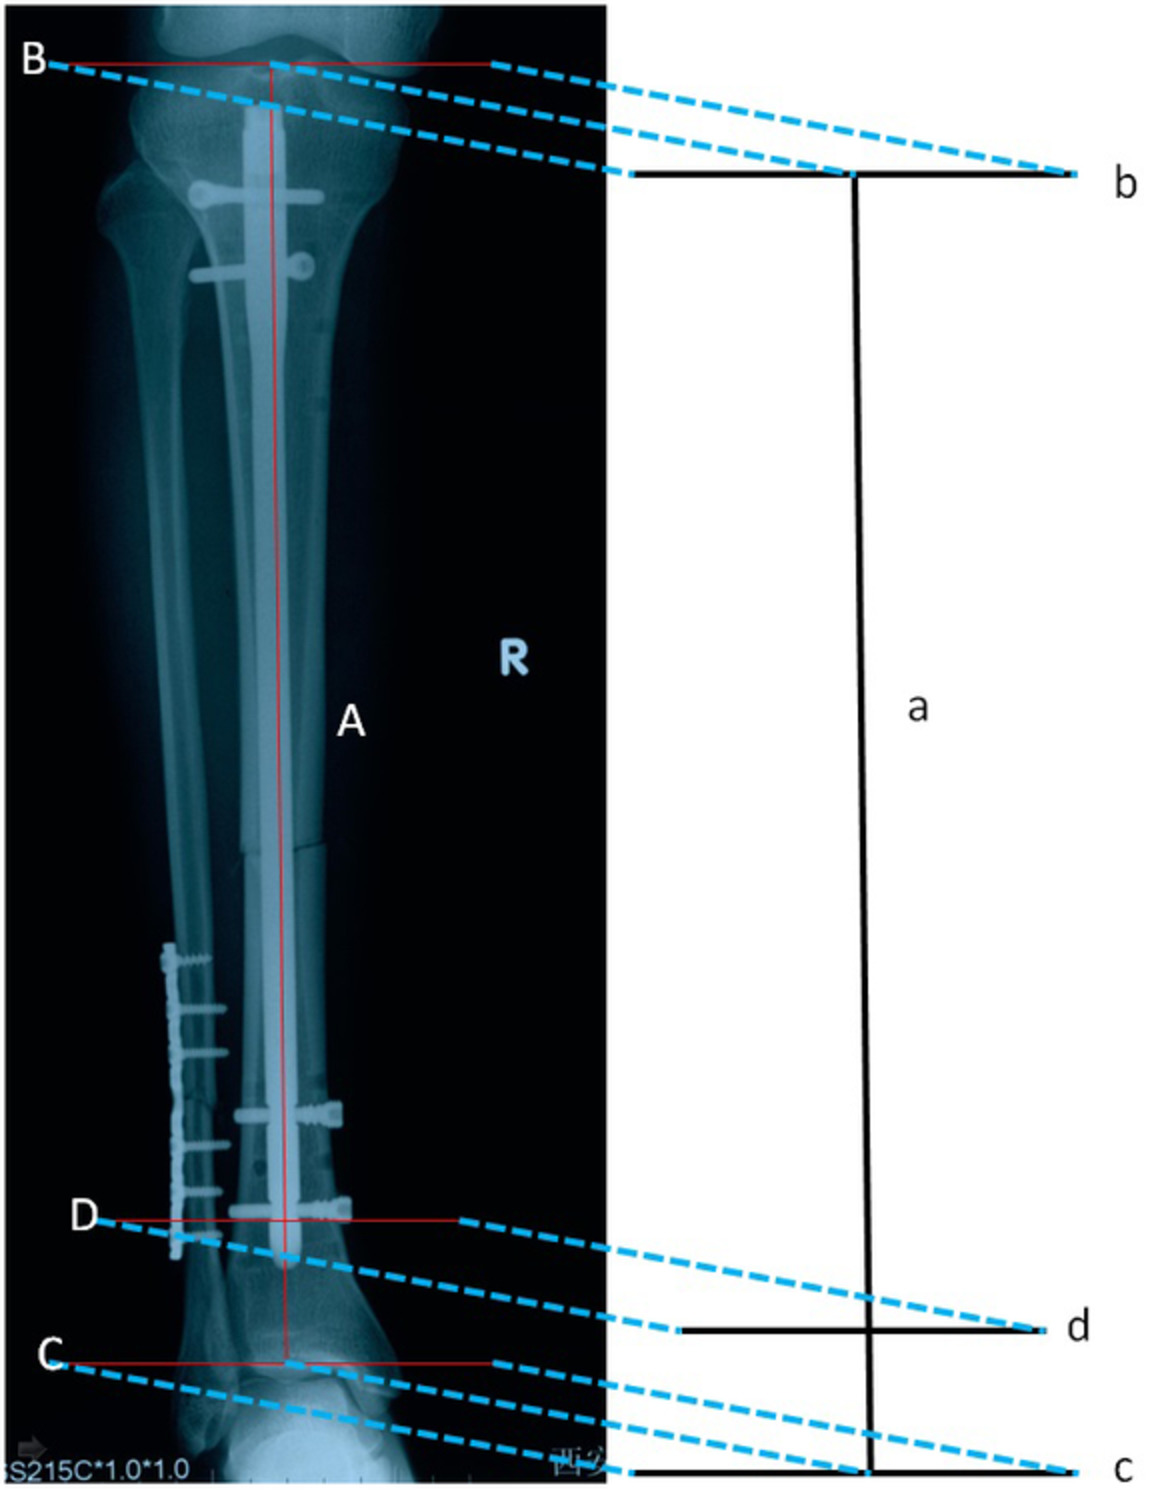

There were four postoperative complications due to surgical technique (Table 2). Three patients (10.7%) developed wound infection. However, one patient in the AS group had only one infection, whereas two patients in the K-wire group had one infection. In the one case in the AS group, the wound was red and swollen, and the healing time was delayed because of open fracture. The wound healed after one debridement, and the other nine cases healed well. In contrast, two of the K-wire patients (11.1%) had wound infection: one patient required only one debridement, and the other had a concomitant deep infection and early implant failure requiring complete serial debridements and re-operation. Three patients (16.7%) required re-operation in the K-wire group: one due to infection and two due to early implant failure. In the AS group, all distal pole fractures of the patella showed bony union, without loosening, falling, pulling out and nonunion of the fractures 6 months after operation. The complication rate was lower in the AS group than that in the K-wire group (P < 0.05). A typical case is shown in Figs 3-5.

TABLE 2. Postoperative complications according to surgical technique Technique n Infection n (%) Nonunion n (%) Implant failure n (%) Reoperation sn (%) AS 10 1 (10%) 0 0 0 K-wire 18 2 (11.1%) 2 (11.1%) 3 (16.7%) 3 (16.7%) Total 28 3 (10.7%) 2 (7.1%) 3 (10.7%) 3 (10.7%) AS, Anchor and Krackow-“8” suture fixation; K-wire, Kirschner wire. image

Anterioposterior and lateral knee radiographs of a 65-year-old female patient. (A,B) Patients with distal pole patellar fractures; (C,D) after treatment with anchor and Krackow-“8” suture fixation.

image

Anterioposterior and lateral knee radiographs of a 52-year-old male patient (A,B) Patients with distal pole patellar fractures; (C,D) after treatment with anchor and Krackow-“8” suture fixation.

Anterioposterior and lateral knee radiographs of a 55-year-old male patient (A,B) Patients with distal pole patellar fractures; (C,D) after treatment with anchor and Krackow-“8” suture fixation.